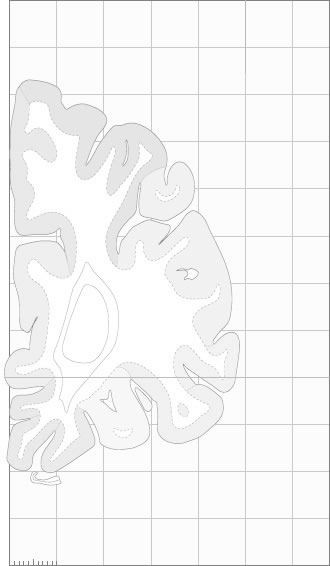

Hi-Resolution Sections · Cells (Nissl Staining) · Virtual Microscopy

Frontal sections (Nissl) from the Atlas Brain:

Schematic

Slice ID:

r1-0251

Plate NR:

04-05

Position:

-40,5 mm